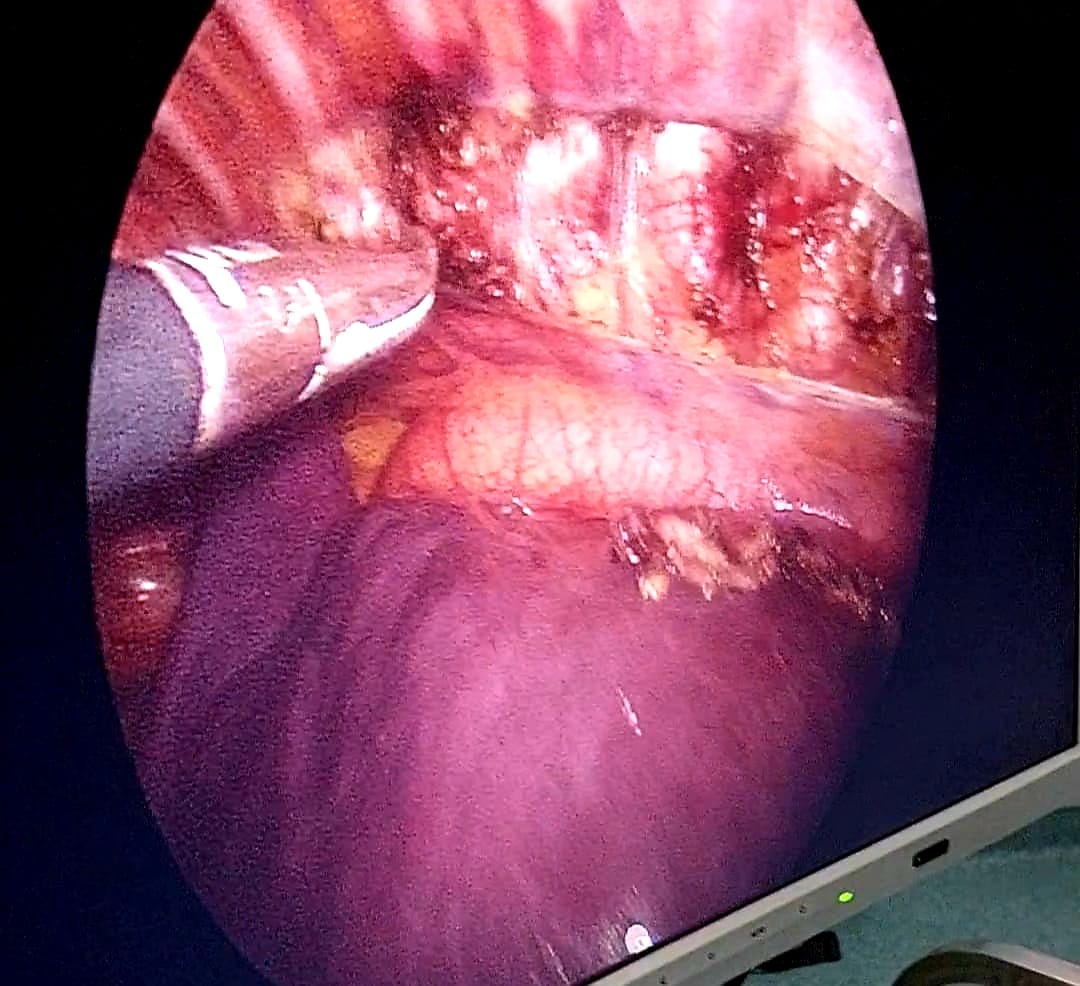

وفي سياق متصل، أوضح الدكتور سيد جلال، مدير فرع التأمين الصحي بمحافظة القليوبية، أن علاج حالة فرط التعرق التعويضي، كانت لطفلة تبلغ من العمر 12 عامًا، وتم إجراء التدخل العلاجي باستخدام تقنية المنظار، لكيّ العصب السمبثاوي، مما ساهم بشكل فعّال في تخفيف معاناة الطفلة وتحسين جودة حياتها.

من جهته، أكد الدكتور محمد كساب، مدير مستشفى بهتيم، أن العملية تمت تحت إشراف فريق طبي متخصص يضم نخبة من الاستشاريين وطاقمًا تمريضيًا عالي الكفاءة، مؤكداً استعداد المستشفى لاستقبال المزيد من الحالات التي تحتاج إلى هذا النوع من التدخلات الدقيقة، مع الاستمرار في تقديم خدمات طبية متطورة تلبي احتياجات المرضى في محافظة القليوبية والمناطق المجاورة.